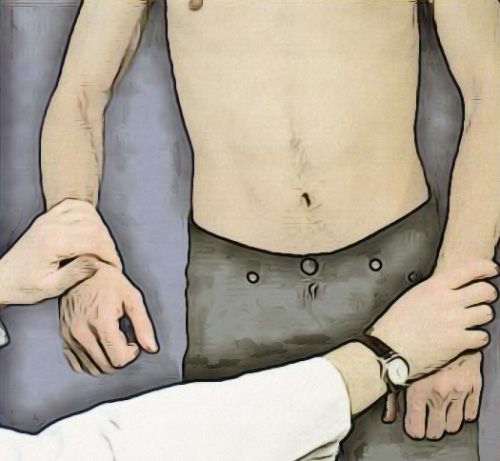

Пальпация плечевого сустава осуществляется путем охвата обеими руками головок плечевых костей (врач находится за спиной пациента), пытаясь глубоко проникнуть кончиками пальцев в суставные щели (рисунок 2). Пальпация грудино-ключичных суставов предполагает выявление болезненности.

Рисунок 2. Пальпация плечевого сустава